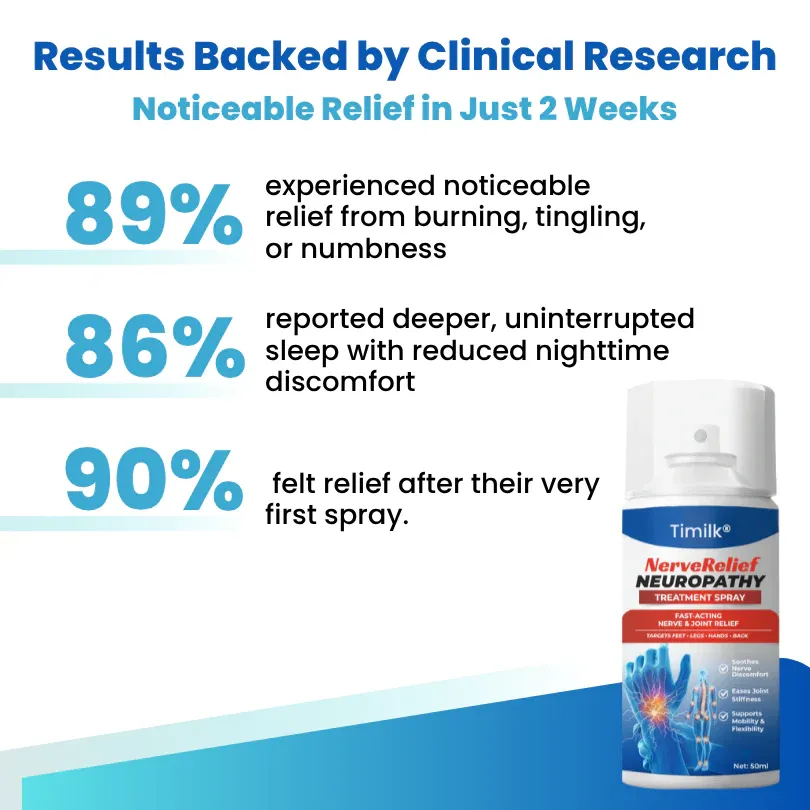

Results Backed by Clinical Research — Noticeable Relief in Just 2 Weeks

89% experienced noticeable relief from burning, tingling, or numbness.

Instead of masking pain, real comfort began restoring confidence in movement.

86% reported deeper, uninterrupted sleep with reduced nighttime discomfort.

90% felt relief after their very first spray.

No waiting months. No rubbing. No greasy mess — just fast, touch-free comfort that lasts.

Based on a 2-week clinical study of 160 participants.